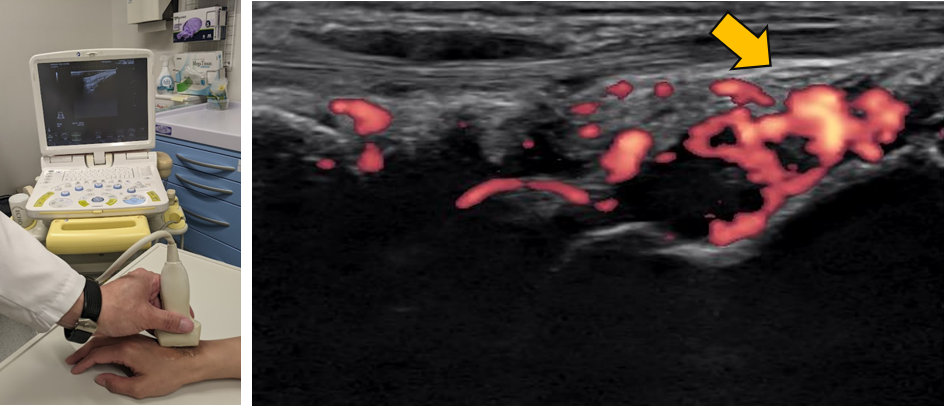

画像:MRI画像で確認される骨髄浮腫(左)と多発している関節の炎症(右)

MRI画像で確認される骨髄浮腫(左)と 多発している関節の炎症(右)